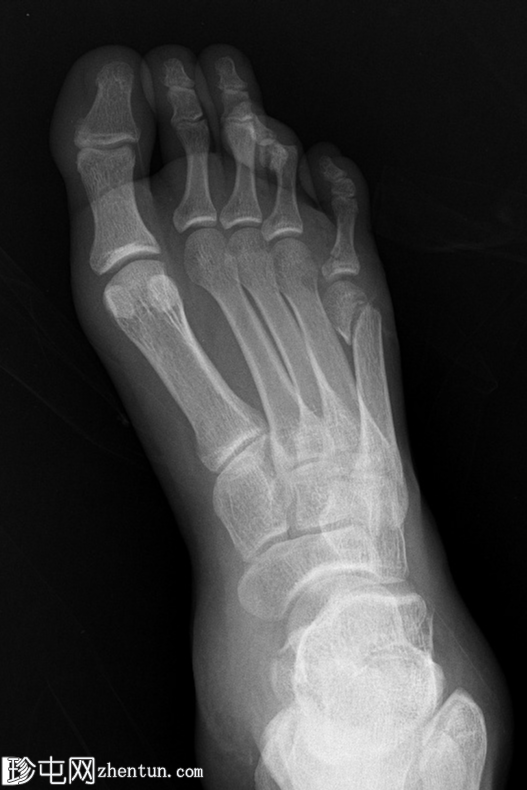

X线片

正位

第四趾近节指间关节(PIPJ)跖侧脱位。

第五趾近节指骨无移位骨折。

第五跖骨颈骨折伴跖侧移位(背侧成角)。

跟骨关节内骨折。